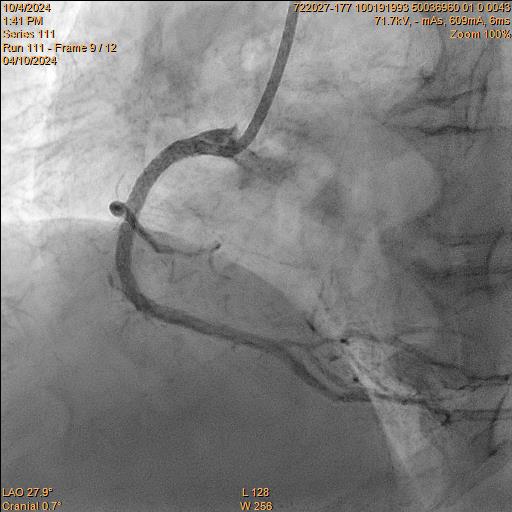

Intervention of RCA Right Coronary Artery was engaged with JR 7Fr Guiding Catheter. Lesion was successful wired with Fielder XT-R and was changed back to workhorse (NS Runthrough) wire. Sequential predilatation using 1.0/15 Sapphire, 1.5/15 Sapphire II Pro, and 2.25/15 Sapphire II Pro was then carried out with Guideplus II assistance; unfortunately, severe balloon underexpansion was noted. Rotational Atherectomy (RA) was attempted 1.25mm Burr for 2 passes at 180k rpm. Lesion was further prepared with 3.0/13 NSE Aperta and 3.0/10 NC Sapphire 24 under Intra-vascular ultrasound (IVUS) guidance before deploying overlapping 3.0/40 Orsiro Mission, 3.5/40 Orsiro Mission and 4.0/18 Orsiro Mission. Repeat IVUS after stent optimization showed stent underexpansion. Hence, intravascular lithrotripsy (IVL) was performed with Shockwave 3.5/12 for a total of 80 shocks, followed by 3.0/10 NC Sapphire stent optimization.

Intervention of RCA Right Coronary Artery was engaged with JR 7Fr Guiding Catheter. Lesion was successful wired with Fielder XT-R and was changed back to workhorse (NS Runthrough) wire. Sequential predilatation using 1.0/15 Sapphire, 1.5/15 Sapphire II Pro, and 2.25/15 Sapphire II Pro was then carried out with Guideplus II assistance; unfortunately, severe balloon underexpansion was noted. Rotational Atherectomy (RA) was attempted 1.25mm Burr for 2 passes at 180k rpm. Lesion was further prepared with 3.0/13 NSE Aperta and 3.0/10 NC Sapphire 24 under Intra-vascular ultrasound (IVUS) guidance before deploying overlapping 3.0/40 Orsiro Mission, 3.5/40 Orsiro Mission and 4.0/18 Orsiro Mission. Repeat IVUS after stent optimization showed stent underexpansion. Hence, intravascular lithrotripsy (IVL) was performed with Shockwave 3.5/12 for a total of 80 shocks, followed by 3.0/10 NC Sapphire stent optimization.